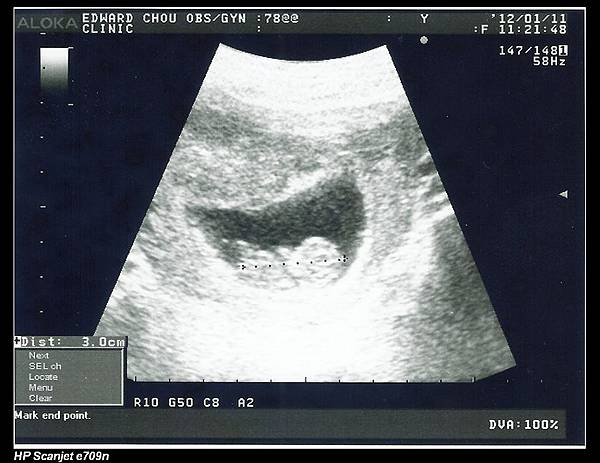

照例還是有超音波檢查。今天超音波儀器一放上馬麻肚肚,余小龍就在裡面動了起來,讓醫師把拔媽麻都驚喜了一下,可是之後他就懶得再表演給大家看了。

余小龍的心跳大約是一分鐘180下,身長已經速速變成3公分了,馬麻給他的便當還有剩一點,醫師說下次看便當就會吃完了。

周醫師還解說了羊膜的位置,還講了很多,但馬麻看著螢幕一心在想著余小龍,居然沒怎麼聽進去,呵!